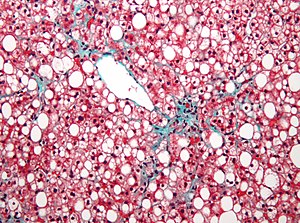

Steatosis. Elastic Masson's trichrome stain. | |

| LM | fatty change (macrovesicular or microvesicular and periportal or centrilobular), negative for ballooning degeneration, negative for significant inflammation - esp. neutrophils |

Features - macrovesicular steatosis.

- One large vacuoles - similar to mature adipose tissue.

- Nucleus is eccentric.

Features - microvesicular steatosis.

- Multiple small (clear) cytoplasmic vacuoles - similar to brown fat, as seen in a hibernoma.

- Nucleus is central.[11]